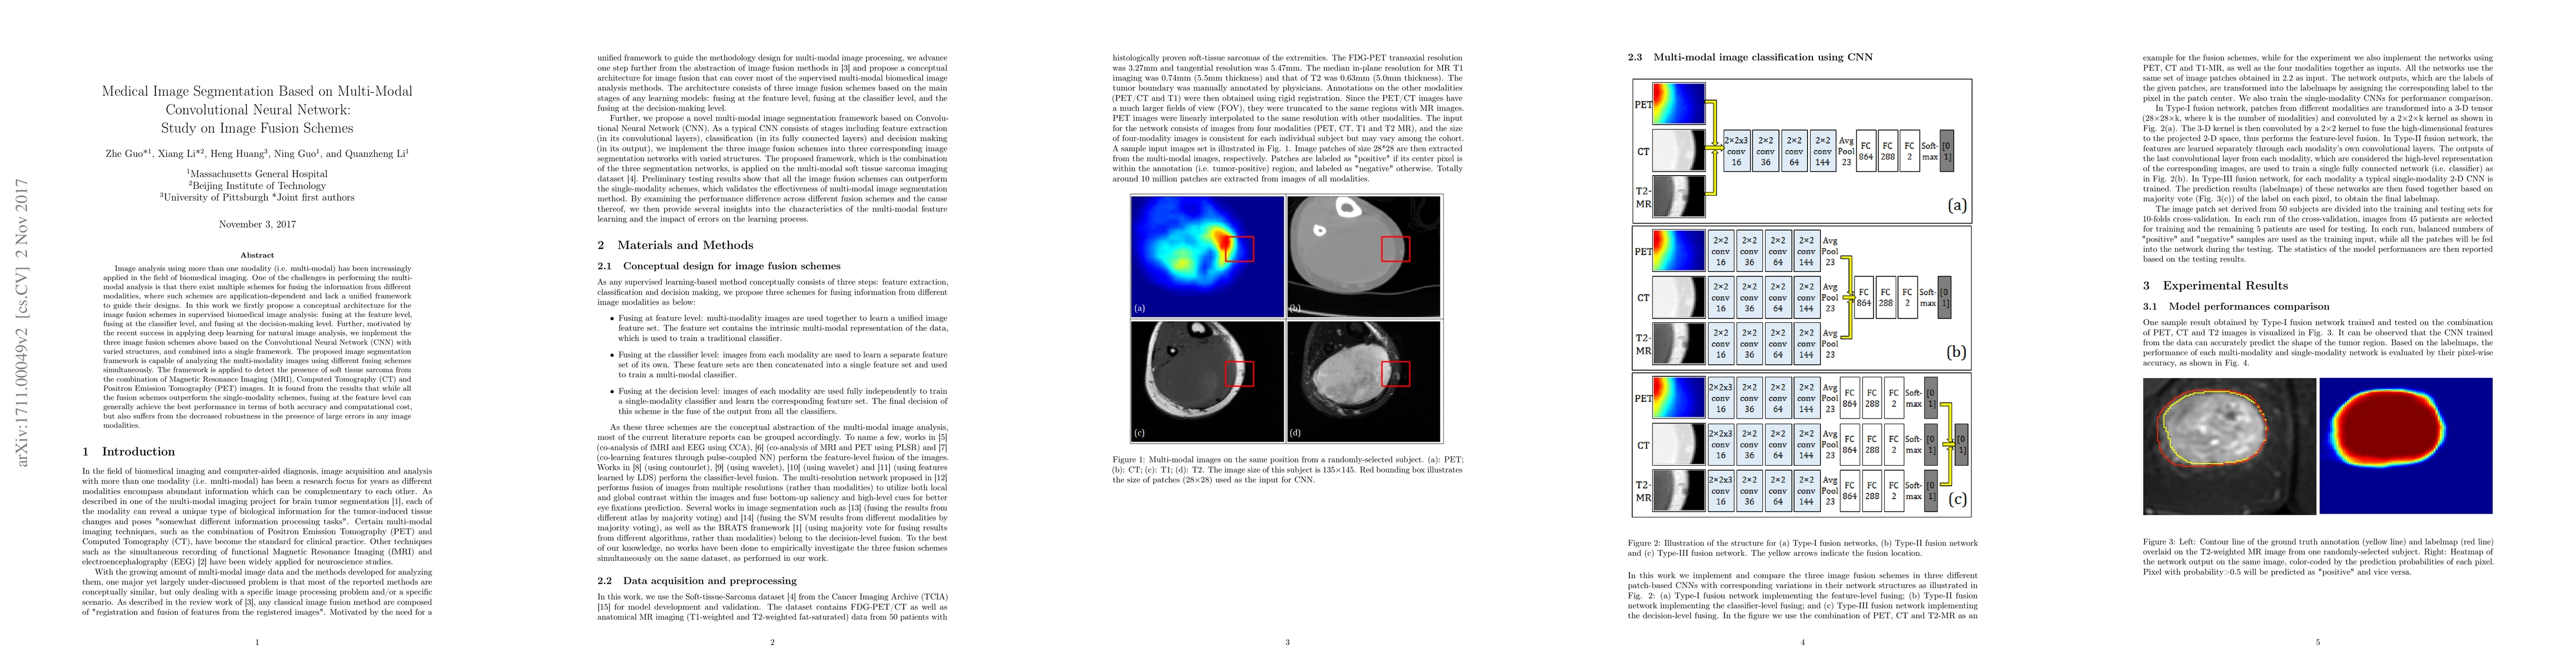

Image analysis using more than one modality (i.e. multi-modal) has been increasingly applied in the field of biomedical imaging. One of the challenges in performing the multimodal analysis is that there exist multiple schemes for fusing the information from different modalities, where such schemes are application-dependent and lack a unified framework to guide their designs. In this work we firstly propose a conceptual architecture for the image fusion schemes in supervised biomedical image analysis: fusing at the feature level, fusing at the classifier level, and fusing at the decision-making level. Further, motivated by the recent success in applying deep learning for natural image analysis, we implement the three image fusion schemes above based on the Convolutional Neural Network (CNN) with varied structures, and combined into a single framework. The proposed image segmentation framework is capable of analyzing the multi-modality images using different fusing schemes simultaneously. The framework is applied to detect the presence of soft tissue sarcoma from the combination of Magnetic Resonance Imaging (MRI), Computed Tomography (CT) and Positron Emission Tomography (PET) images. It is found from the results that while all the fusion schemes outperform the single-modality schemes, fusing at the feature level can generally achieve the best performance in terms of both accuracy and computational cost, but also suffers from the decreased robustness in the presence of large errors in any image modalities.